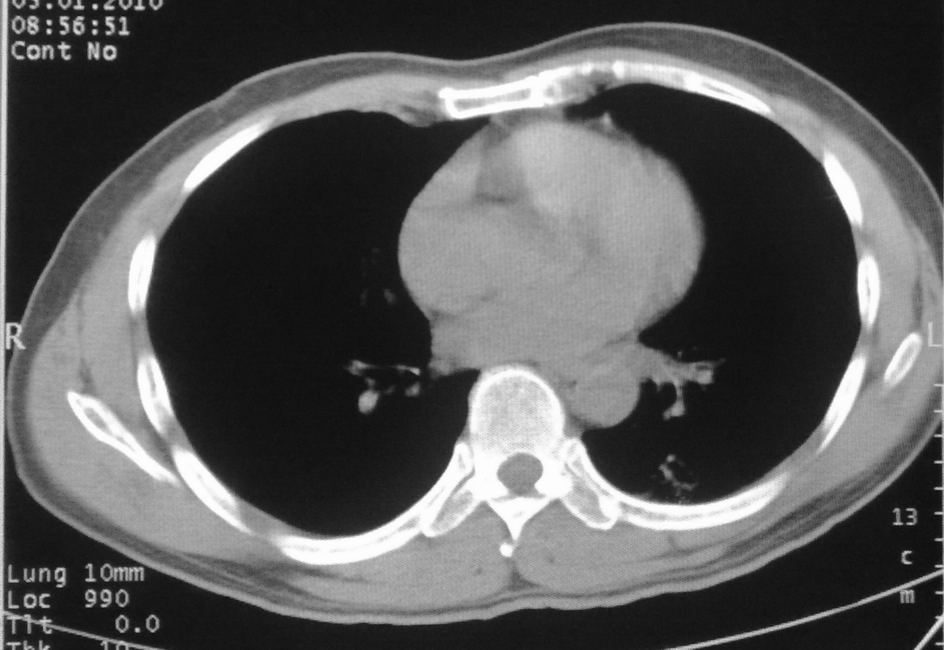

男,51岁,左胸前区不适数天。

薄壁空洞,边缘毛刺,胸膜凹陷,考虑肺癌,结核不排除。

肺癌

考虑左肺下叶感染性病变。

考虑左肺下叶感染性病变,不除外肺栓。